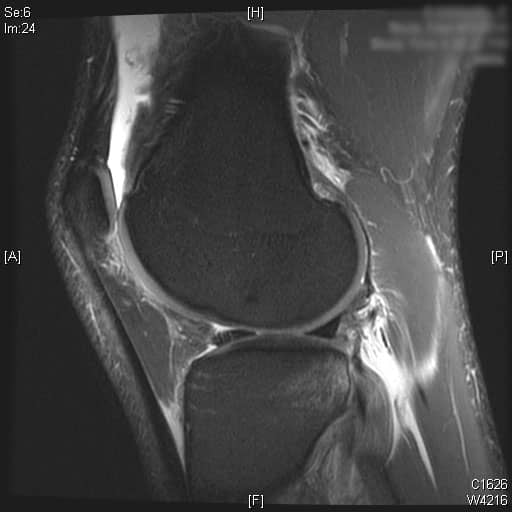

Initial imaging consists of a knee trauma radiograph series including anteroposterior, lateral and patellar views.1 The images should be closely reviewed for bony avulsion fractures and any associated bony injuries. The Segond sign (small avulsion off the lateral tibial plateau) represents a lateral capsular avulsion which should raise suspicion for an ACL rupture.2 In select patients at risk for knee osteoarthritis, posterior to anterior, 45 degree flexion weight-bearing films may be obtained.3 Knee MRI is the most sensitive and specific in diagnosing ACL injuries. Bone contusions of the lateral femoral condyle and posterior tibial plateau are the most common associated finding.4 Injuries to the menisci, collateral ligaments and posterior cruciate ligament are also reliably detected on MRI. Knowledge of concomitant knee injuries is essential for preoperative planning.

Complete ACL rupture is seen on the sagittal T2 MRI images. Also, bone marrow edema is seen on the posterior third of the lateral tibial plateau. Cartilage on the medial and lateral femoral condyle alone with the patella is preserved. Moderate joint effusion is visualized on the T2 MRI images.